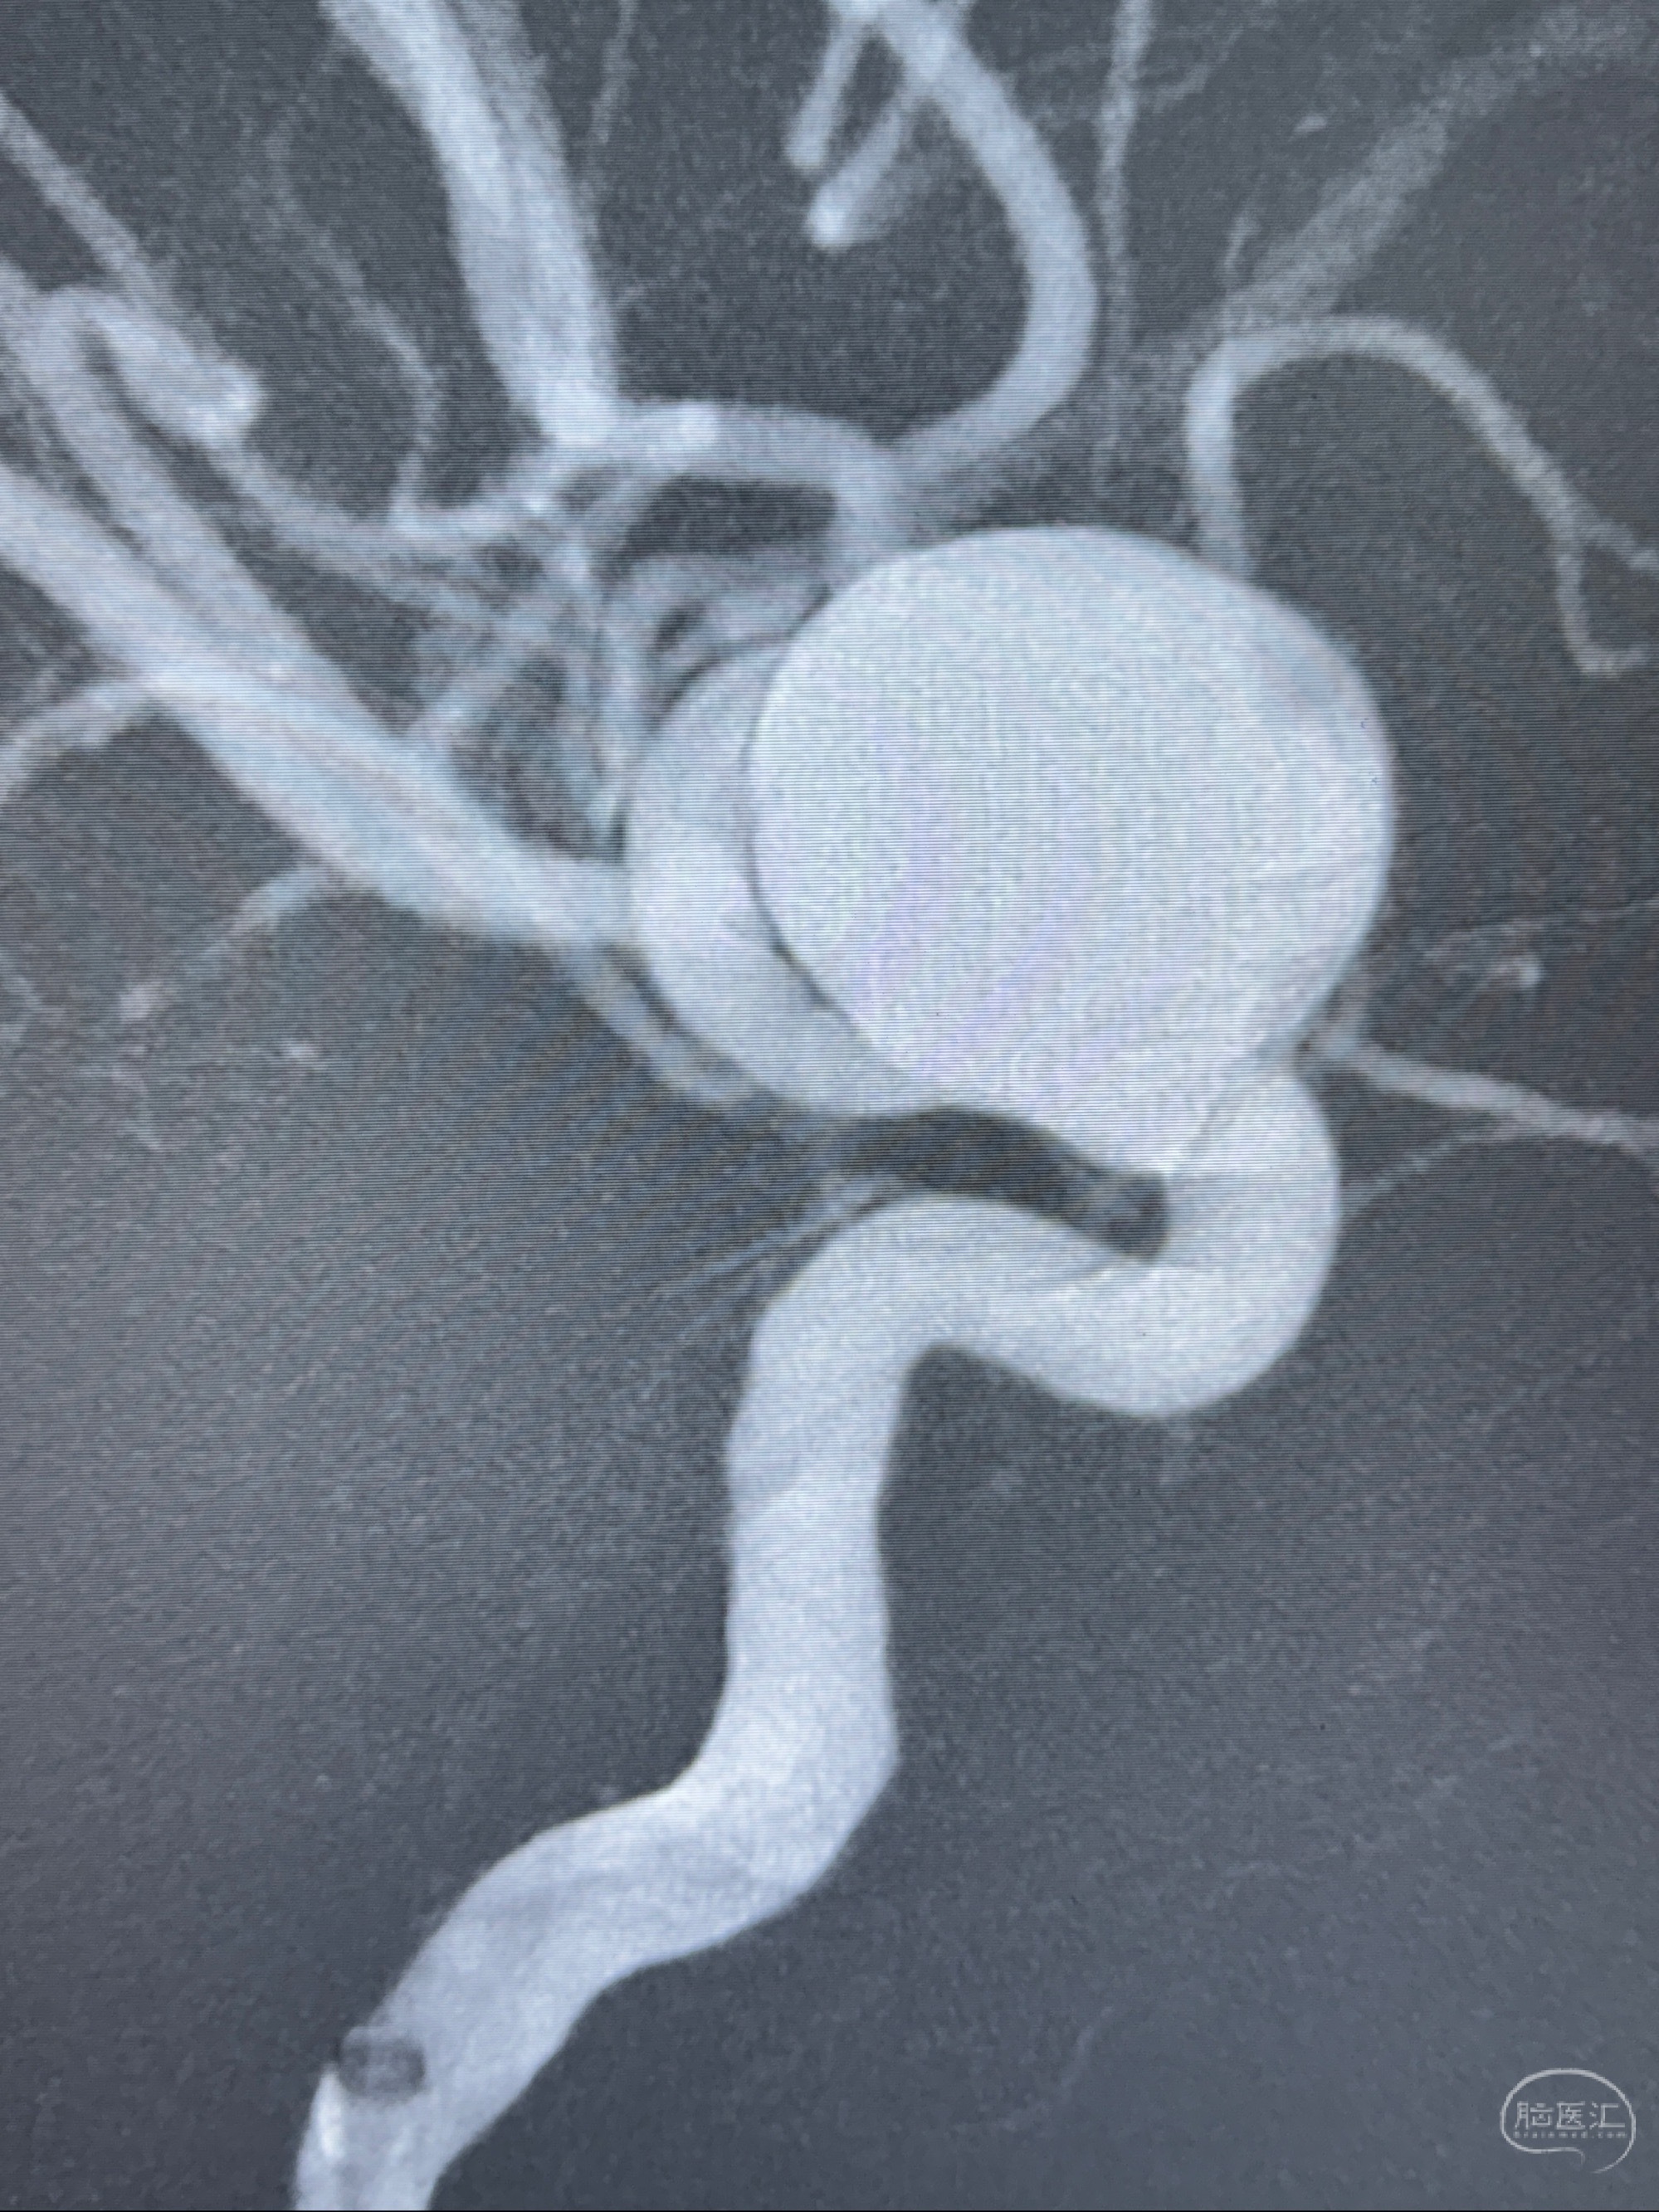

测量动脉瘤的大小:16*13.8*7.6mm大小,较原先变大,考虑双抗后瘤内血栓溶解可能

2023-12-27术后第十天复查DSA

支架贴壁佳,但可见射流,咋办?

2024-01-08全麻下再行植入密网支架一枚

Tubridge 4.5-35mm

支架植入顺利,贴壁佳,支架内血流通畅,动脉瘤内血液滞留明显